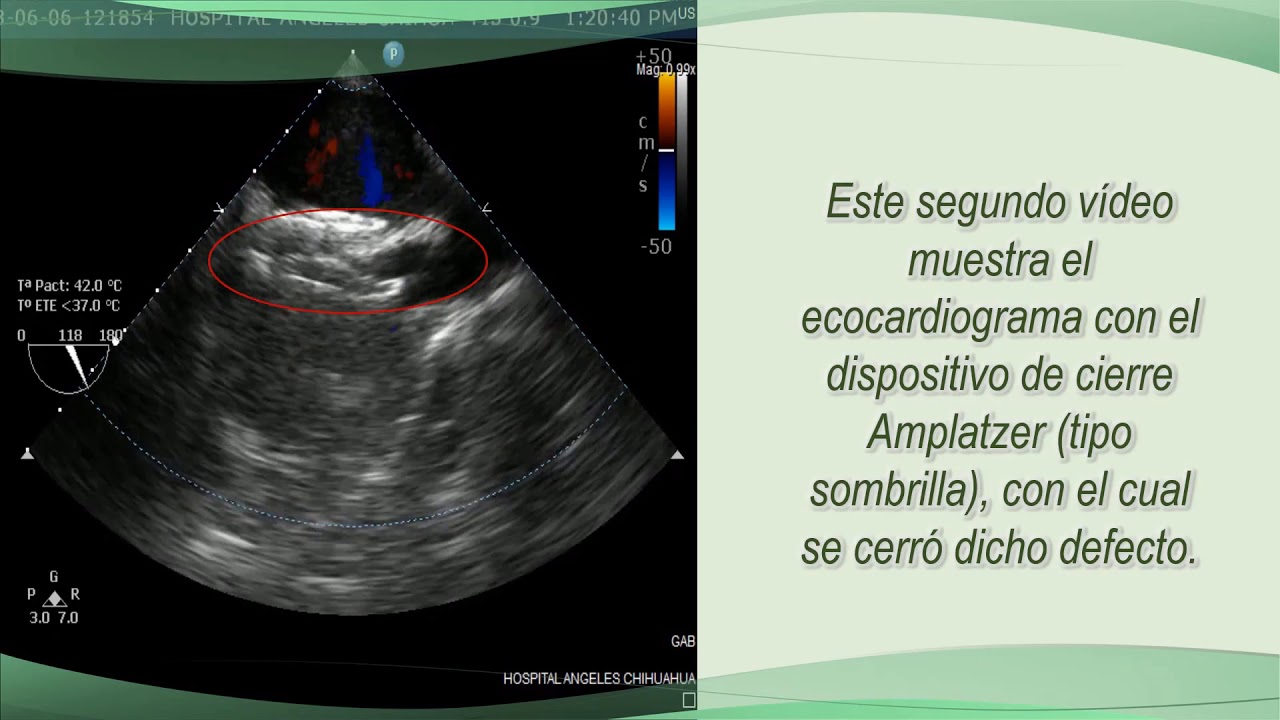

Especialista en Cateterismo CardiacoMás de 10 años de experiencia en IntervencionismoEgresado del Hosp Clinico San Carlos de Madrid Esp

Cateterismo cardíaco terapéutico y diagnóstico